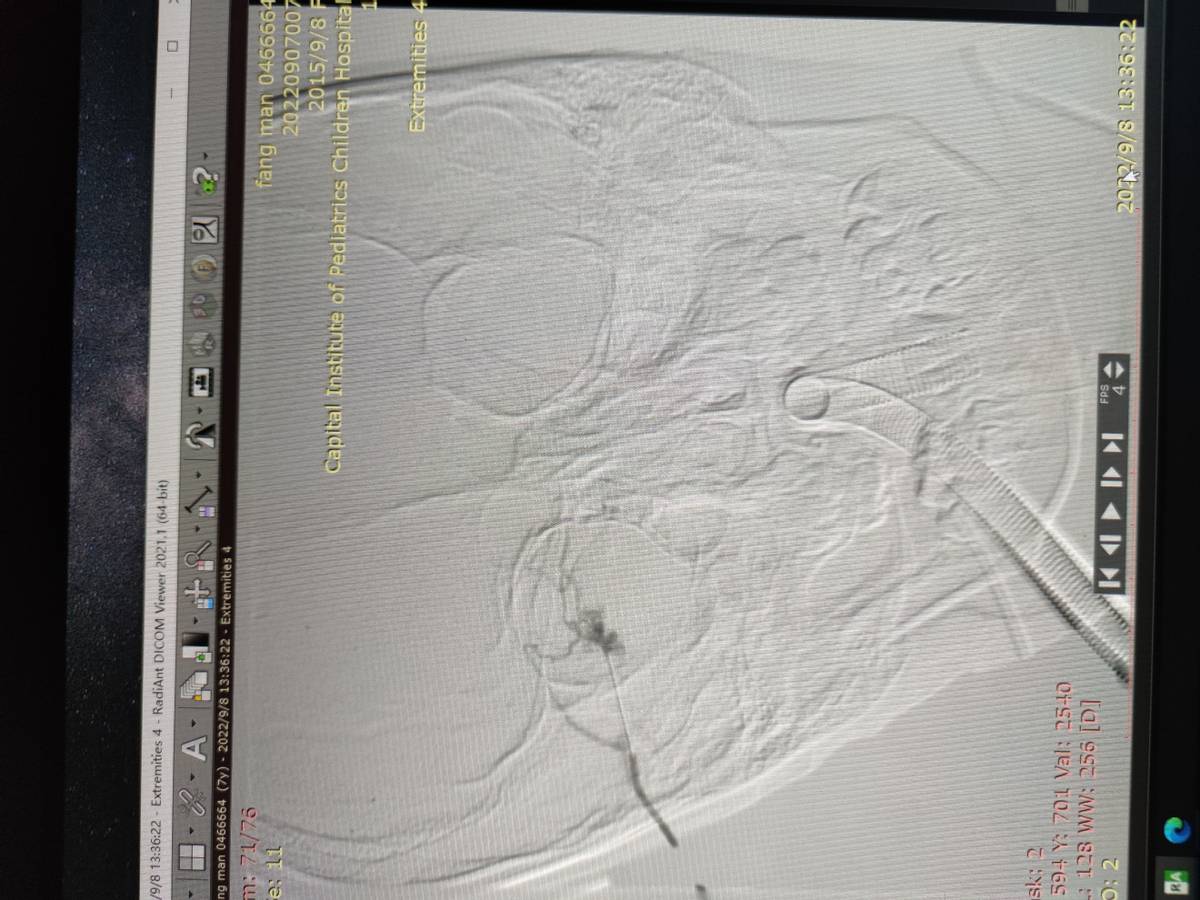

孩子做完检查后,全麻下很顺利的进行了动脉造影、药物灌注、影像引导下硬化治疗等一系列介入手术治疗,手术约40分钟,术后第一天就平安回家了。

术中影像